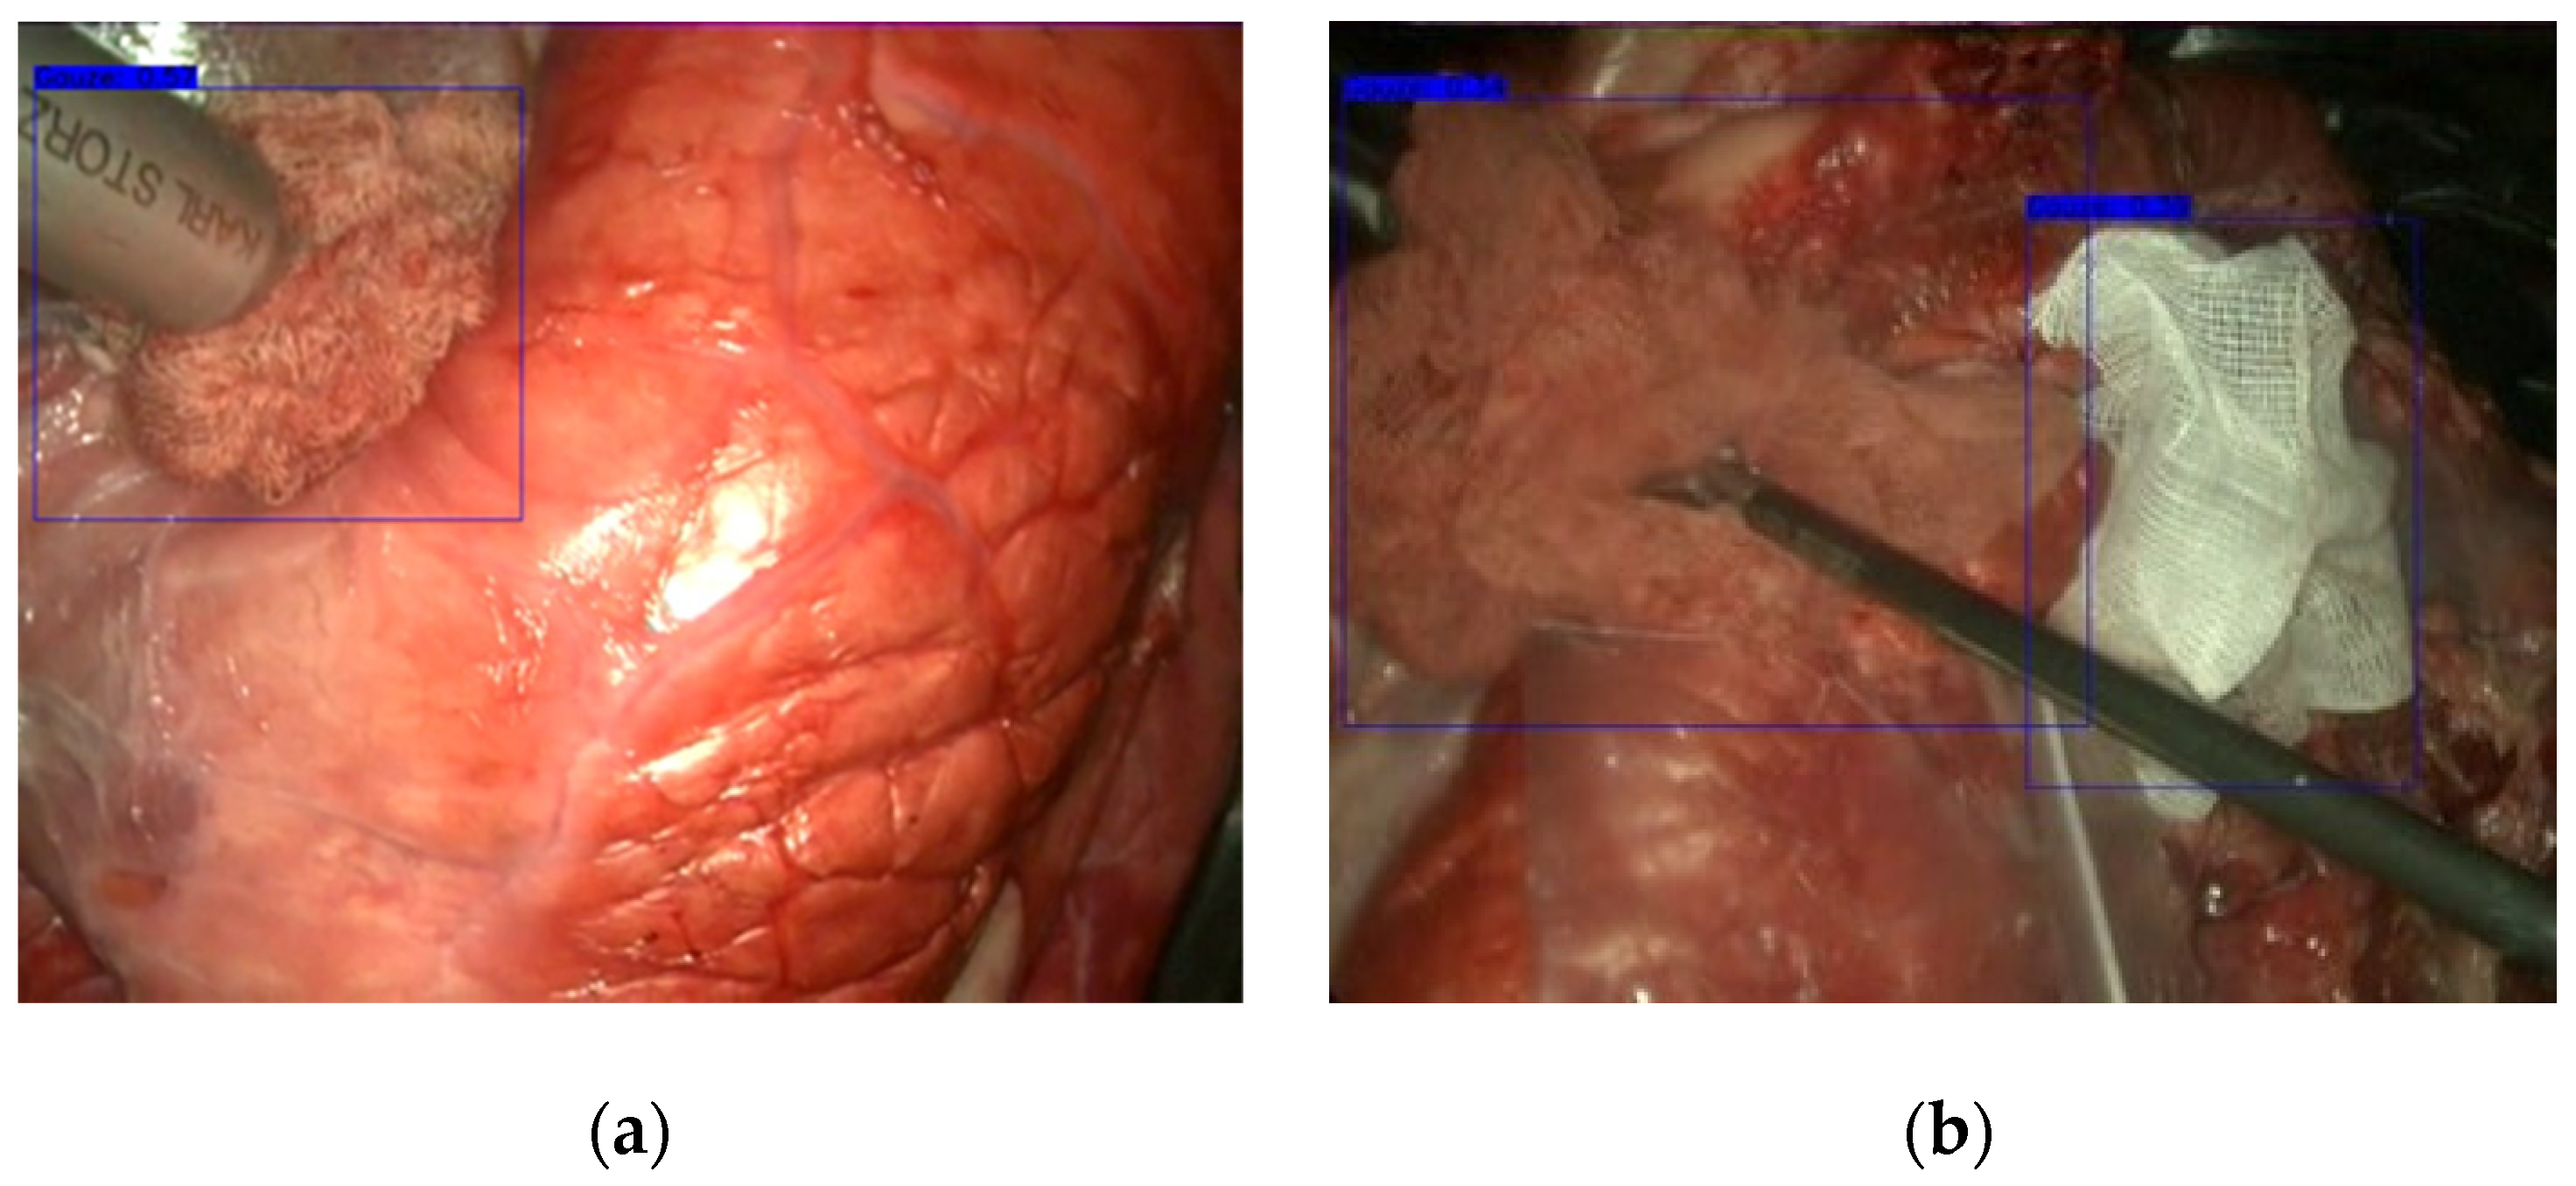

3.1. Gauze Detection